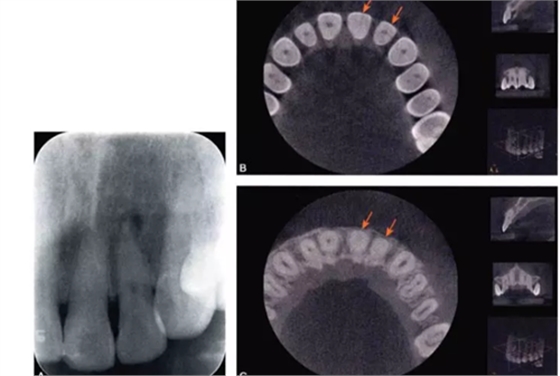

完全鈣化根管在X線片上的表現(xiàn)是根管影像模糊,密度增高,根管密度與周圍的牙本質(zhì)密度接近,甚至無法區(qū)分根管與牙本質(zhì)的影像。有些根管,可表現(xiàn)為根管影像時(shí)斷時(shí)續(xù)或模糊不清,為不完全鈣化根管表現(xiàn)(圖4-1A)。細(xì)小根管的病例在X線片上,根管影像隱約可見,與同名牙或鄰牙相比,根管較為細(xì)小影像清晰度降低。

目前,小視野CBCT物理層厚可達(dá)76m,對根管系統(tǒng)的顯示明顯優(yōu)于其他影像學(xué)手段。觀察根管的CBCT圖像,冠根向橫斷面能夠比較直觀地顯示根管中央的鈣化情況。觀察時(shí)可從髓底開始,將橫截面斷層由冠方向根尖方向推移,逐層觀察。正常根管位于牙根的中央部位,呈圓形或橢圓形暗影,與周圍的牙本質(zhì)所顯示的致密白色影像有明顯區(qū)別。細(xì)小鈣化根管表現(xiàn)為橫截面中央的暗影變淡、消失,與周圍牙本質(zhì)影密度接近或相同,與同一患牙其他根管及正常鄰牙的根管影像則有明顯區(qū)別。通過CBCT,還可以測量鈣化根管的長度及范圍(圖4-1B、C)。